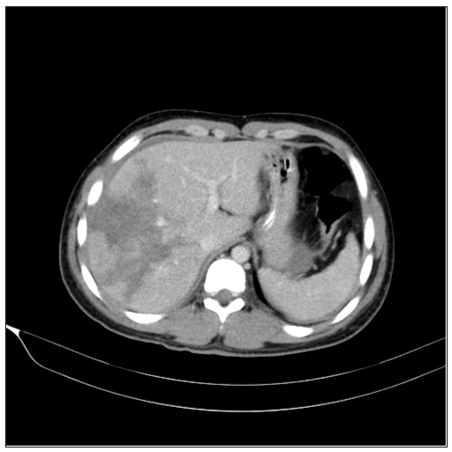

Hepatic Laceration/Contusion -CT